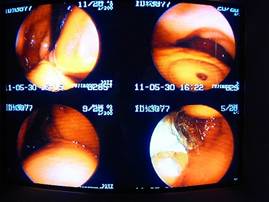

内視鏡での様子。

胃内にゴムボールを確認しました。

思っていたよりも結構固いボールで、

安全に摘出することは難しいと考え、開腹手術に切り替えました。